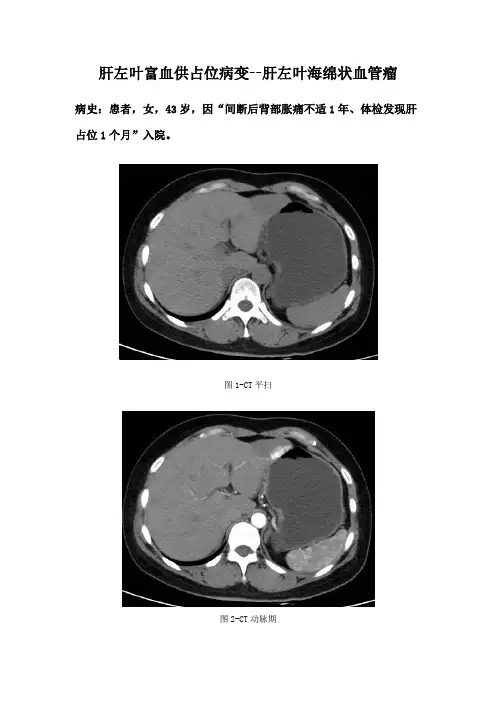

肝左叶富血供占位病变--肝左叶海绵状血管瘤病史:患者,女,43岁,因“间断后背部胀痛不适1年、体检发现肝占位1个月”入院。

图1图2图3图4CT平扫(图1):肝左叶见类圆形低密度影,边界清晰。

CT增强动脉期(图2)肝左叶病灶边缘迅速呈斑片样明显强化。

CT增强门脉期(图3)病灶强化明显,向内部填充呈结节样强化改变。

CT增强延迟期(图4)强化程度减低,仍高于周围正常肝实质,几乎完全填充病灶。

影像描述:肝左叶见类圆形低密度影,边界清晰,大小为4.0cmx2.8cm。

增强动脉期边缘斑片样明显强化,门脉期及延迟期呈向心性填充式强化,高于周围肝实质。

影像诊断:肝左叶海绵状血管瘤分析思路:1.临床病史:中年女性,体检发现,提示良性或低度恶性肿瘤。

无肝炎病史及AFP升高,肝细胞肝癌概率减低。

无口服避孕药及激素服用史,腺瘤概率减低。

2.部位及形态:病变位于肝脏左叶,边界清晰,提示良性可能。

3.CT增强:对肝脏肿瘤诊断有鉴别意义。

本例为动脉期边缘斑片样明显强化,门脉期及延迟期持续呈填充式强化,强化程度明显高于周围肝实质,即为“早出晚归”强化方式,为典型海绵状血管瘤强化方式,本例符合。

肝细胞肝癌具有特征性“快进快出”的强化方式,即动脉期迅速强化,门脉期强化程度快速减低,可见假包膜形成,本例不符。

腺瘤因含有脂肪呈低密度或合并出血呈高密度,增强因完全由肝动脉供血,动脉期快速均匀强化,门脉期及延迟期强化程度逐渐减低与肝实质相同,本例不符。

最后诊断:肝左叶海绵状血管瘤。